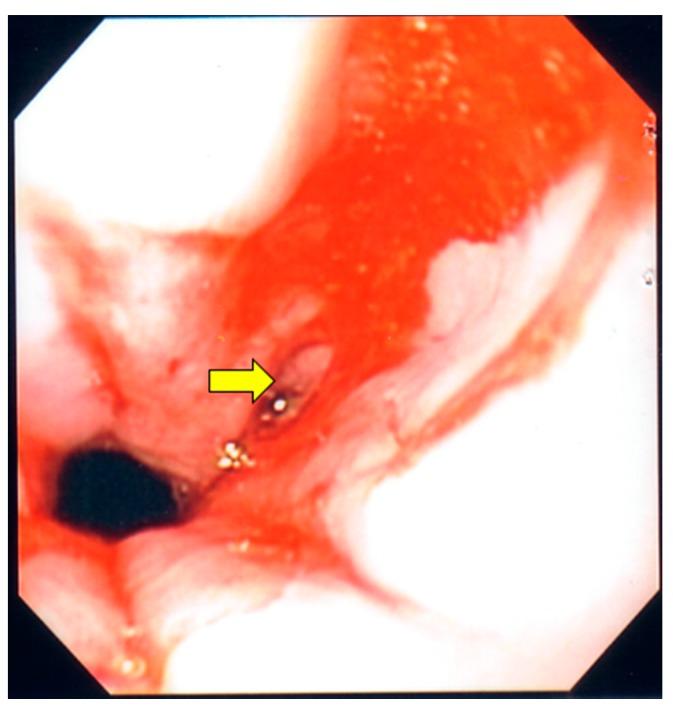

Opportunistic infections of the gastrointestinal tract are well-documented complications of patients with acquired immunodeficiency syndrome (AIDS). However, concomitant infection by and cytomegalovirus has been described rarely. We present the case of an HIV patient with a CD4 count of 20 cells/uL who was admitted with odynophagia and weight loss. Endoscopic evaluation revealed ulcerations in the esophagus and colon, and a mass formation in cecum. Histology revealed budding yeasts in the cecum and a transverse colon consistent with Urine antigen was positive. Esophageal tissue disclosed viral cytopathic changes. Immunostaining was positive for cytomegalovirus in the esophagus and transverse colon. The patient was started on appropriate antifungal and antiviral treatment with complete resolution of his symptoms. To our knowledge, this is the fifth case of and cytomegalovirus co-infection of the gastrointestinal tract in a patient with AIDS. We also review the literature for similar cases in regards to clinical presentation and the type of gastrointestinal involvement.

胃肠道机会性感染是获得性免疫缺陷综合征(AIDS)患者有充分文献记载的并发症。然而,同时感染[某种真菌名称未给出]和巨细胞病毒的情况鲜有报道。我们报告一例CD4细胞计数为20个/微升的HIV患者,因吞咽痛和体重减轻入院。内镜检查发现食管和结肠有溃疡,盲肠有肿物形成。组织学检查显示盲肠和横结肠有芽生酵母,符合[某种真菌名称未给出]感染。尿抗原检测呈阳性。食管组织显示病毒细胞病变。食管和横结肠免疫染色巨细胞病毒呈阳性。患者开始接受适当的抗真菌和抗病毒治疗,症状完全缓解。据我们所知,这是艾滋病患者胃肠道同时感染[某种真菌名称未给出]和巨细胞病毒的第五例。我们还就临床表现和胃肠道受累类型回顾了相关文献中的类似病例。